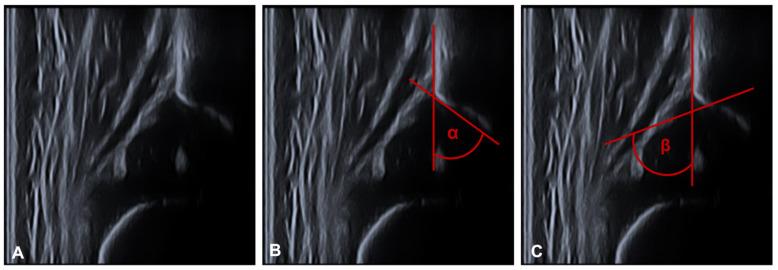

Closed reduction followed by spica casting is a conservative treatment for developmental dysplasia of the hip (DDH). Magnetic resonance imaging (MRI) can verify proper closed reduction of the dysplastic hip. Our aim was to find prognostic factors in the first MRI to predict the possible outcome of the initial treatment success by means of ultrasound monitoring according to Graf and the further development of the hip dysplasia or risk of recurrence in the radiological follow-up examinations. A total of 48 patients (96 hips) with DDH on at least one side, and who were treated with closed reduction and spica cast were included in this retrospective cohort study. Treatment began at a mean age of 9.9 weeks. The children were followed for 47.4 months on average. We performed closed reduction and spica casting under general balanced anaesthesia. This was directly followed by MRI to control the position/reduction of the femoral head without anaesthesia. The following parameters were measured in the MRI: hip abduction angle, coronal, anterior and posterior bony axial acetabular angles and pelvic width. A Graf alpha angle of at least 60° was considered successful. In the radiological follow-up controls, we evaluated for residual dysplasia or recurrence. In our cohort, we only found the abduction angle to be an influencing factor for improvement of the DDH. No other prognostic factors in MRI measurements, such as gender, age at time of the first spica cast, or treatment involving overhead extension were found to be predictive of mid-term outcomes. This may, however, be due to the relatively small number of treatment failures.

闭合复位后髋人字石膏固定是治疗发育性髋关节发育不良(DDH)的一种保守方法。磁共振成像(MRI)可验证发育不良髋关节的闭合复位是否恰当。我们的目的是在首次MRI检查中寻找预后因素,以通过Graf超声监测预测初始治疗成功的可能结果,以及髋关节发育不良的进一步发展或放射学随访检查中的复发风险。本回顾性队列研究纳入了48例至少一侧患有DDH且接受闭合复位和髋人字石膏固定治疗的患者(96髋)。治疗开始时的平均年龄为9.9周。这些儿童平均随访47.4个月。我们在全身平衡麻醉下进行闭合复位和髋人字石膏固定。随后直接在未麻醉状态下进行MRI检查以控制股骨头的位置/复位情况。在MRI中测量以下参数:髋关节外展角、冠状面、前后位骨轴髋臼角和骨盆宽度。Graf α角至少为60°被认为是成功的。在放射学随访检查中,我们评估有无残余发育不良或复发情况。在我们的队列中,我们仅发现外展角是DDH改善的一个影响因素。在MRI测量中未发现其他预后因素,如性别、首次髋人字石膏固定时的年龄或涉及过头伸展的治疗方法,可预测中期结果。然而,这可能是由于治疗失败的病例数相对较少。